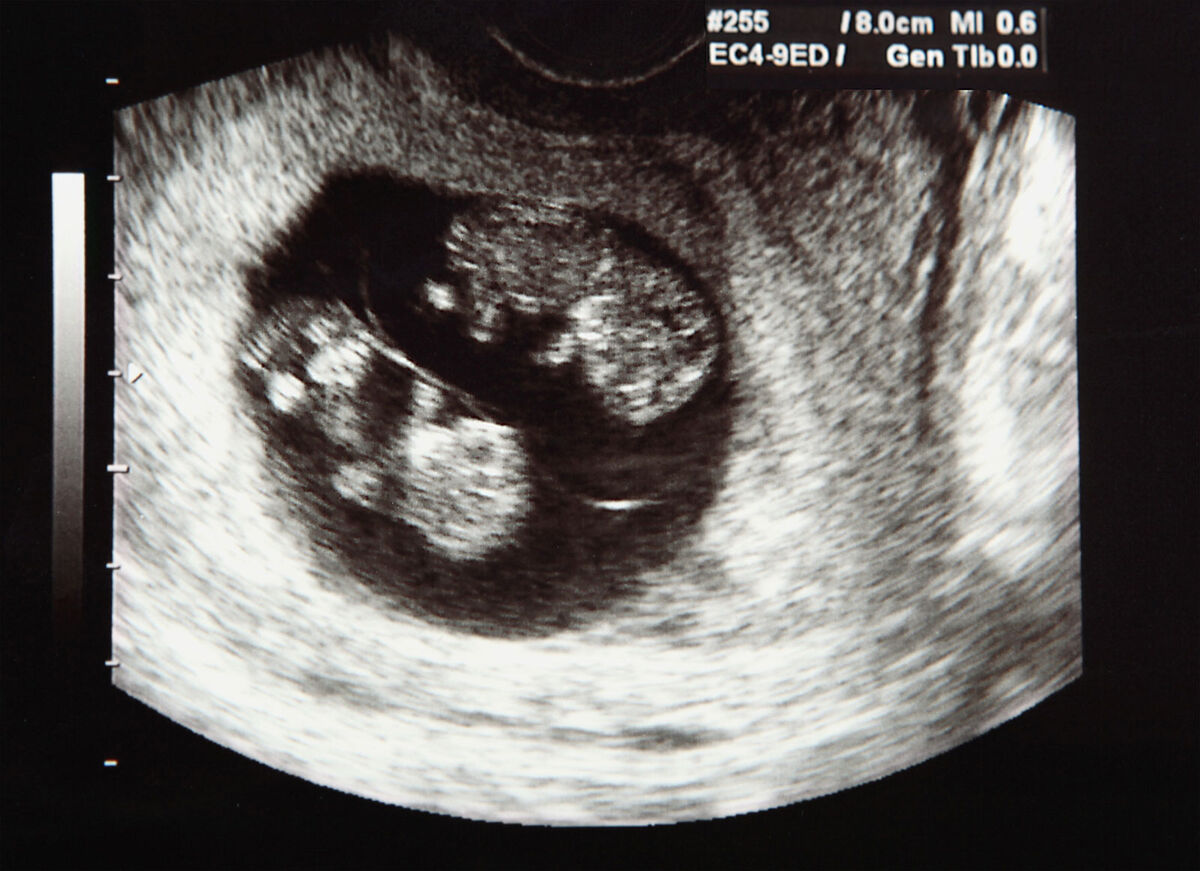

- For ultrasounds to check on the babies' health, the placental function, the fundal height of your uterus and the amounts of amniotic fluid